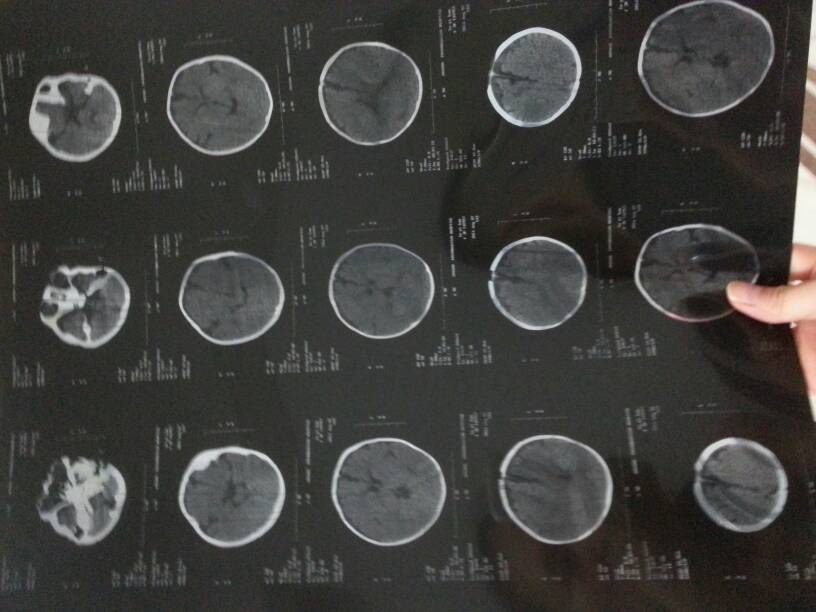

孩子4个月14天了,在4个月孩子还不会抬头去医院检查做脑ct结果是双侧额叶蛛网膜下腔略增宽,脑实质未见局限性低密度影,各脑室大小、形态、位置基本正常,脑沟略加深,中线结构未见移位。后医生说脑发育不良,需要住院康复治疗,治疗10天能台头了。出院的时候医生说20天后再来复查。严重吗?请帮忙详解下吧